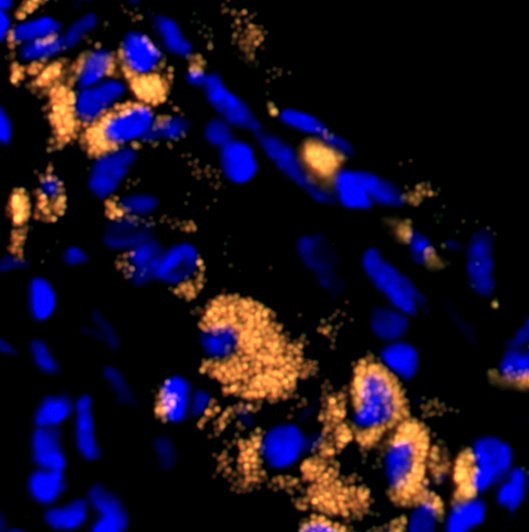

A central pillar of my research program is the investigation of immune-mediated mechanisms underlying myocardial ischemia–reperfusion (I/R) injury in related cardiac pathologies. I have modified and optimized murine models of myocardial ischemia–reperfusion to enable unbiased, reproducible studies of immune responses following cardiac ischemic injury, allowing precise temporal dissection of inflammatory and reparative phases after prolonged ischemia–reperfusion.

Using this platform, I have defined the molecular and cellular dynamics of innate and adaptive immune responses following myocardial ischemia–reperfusion and characterized how immunomodulatory interventions, including cyclosporine A, influence immune activation and functional outcomes after myocardial infarction.

In parallel, my work identified cardiac myosin–specific tissue-resident memory T cells as critical drivers of immune checkpoint inhibitor–associated myocarditis using a clinically relevant two-hit mouse model of immune reactivation, providing mechanistic insight into how maladaptive immune memory triggers severe cardiac inflammation.

Together, these studies establish a unified framework for understanding immune-driven cardiac injury and repair and support the development of targeted strategies to improve outcomes of heart disease.